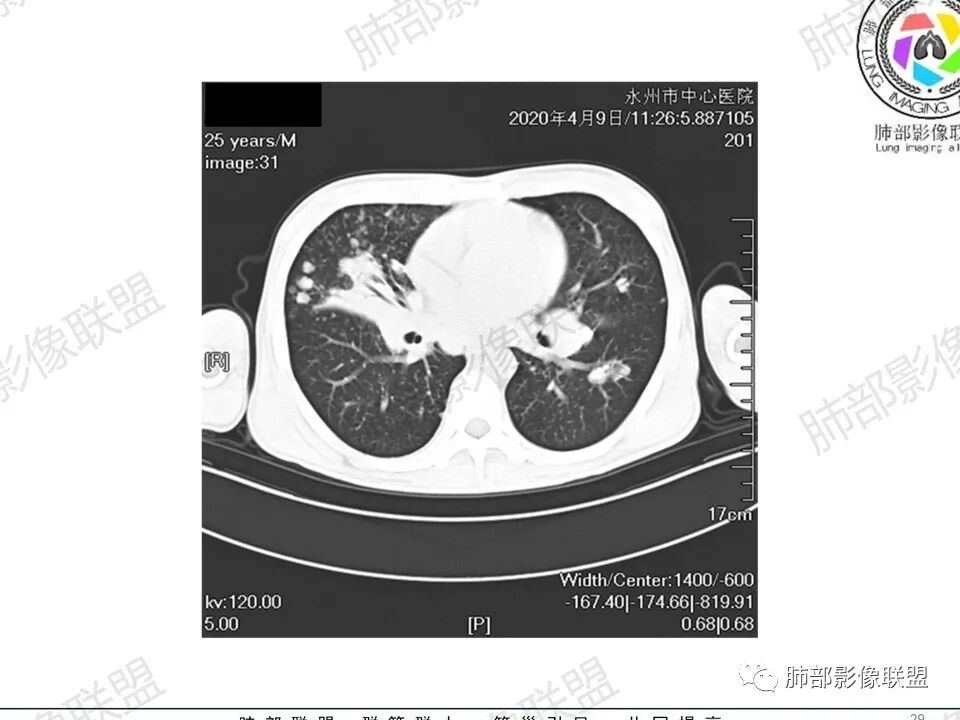

3、影像表现:双肺散在斑片影及结节影,部分结节内可见血管穿行,斑片影沿支气管血管束分布,近胸膜侧病变收缩不明显。部分中央淋巴间质增厚,小叶间隔增厚。病灶内支气管穿行,部分支气管略扩张。局部小结节呈串珠样改变。纵隔、肺门区、锁骨上及腋窝淋淋巴结肿大,部分有融合。心腔低密度。脾大。

2.双肺多发片影及结节影,边界可分辨,右肺中上叶较为密集,没有胸膜下分布优势。病灶实性密度为主,未见钙化及液化。

5.双肺门及纵隔淋巴结显著增大,这改变相当显眼。这里强调“双肺门”及“多发”!

增大的淋巴结密度偏低且均匀。此外患者有体表淋巴结增大。

1.临床表现明显,纵隔及双肺门淋巴结显著肿大,临床最为担心的还是淋巴瘤!

尤其患者有贫血及脾脏增大,又有体表淋巴结增大时,这也是临床相对常见的情形。

淋巴瘤肺部浸润表现多样,多发结节影是其最常出现的影像学改变,尤其是霍奇金病。

2.右肺多发微小结节影,部分沿血管束分布,尽管未见小叶间隔改变,但双肺门淋巴结增大确实应当首先排除结节病,但经验上说,结节病的增大淋巴结密度往往较高、较密实,边界往往清楚,“独立性”很强,绝无“融合之嫌”!此外,较少出现贫血、脾大,临床表现也往往较轻微。